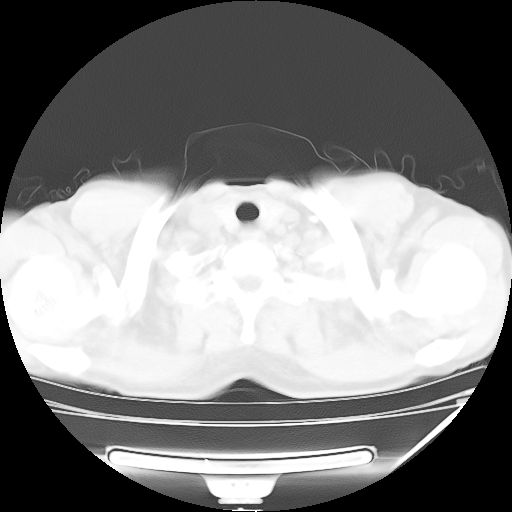

男,59岁,“结核性胸膜炎”30余年,胸部经常疼痛,多次x检查提示“肺部”炎症。腹部疼痛5日,b超提示:“肝内短管结石,余显示不清,建议进一步检查。”

两肺结核并右侧胸腔积液;脾脏、腹腔及腹膜后淋巴结结核[陈旧性];肝内胆管结石